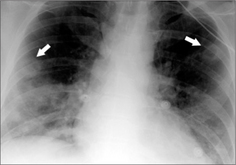

Figure 21.3 Multiple nodules. Male. Age 38. Intravenous drug user. Endocarditis. Lung abscesses. Two of the nodules are cavitating (arrows).